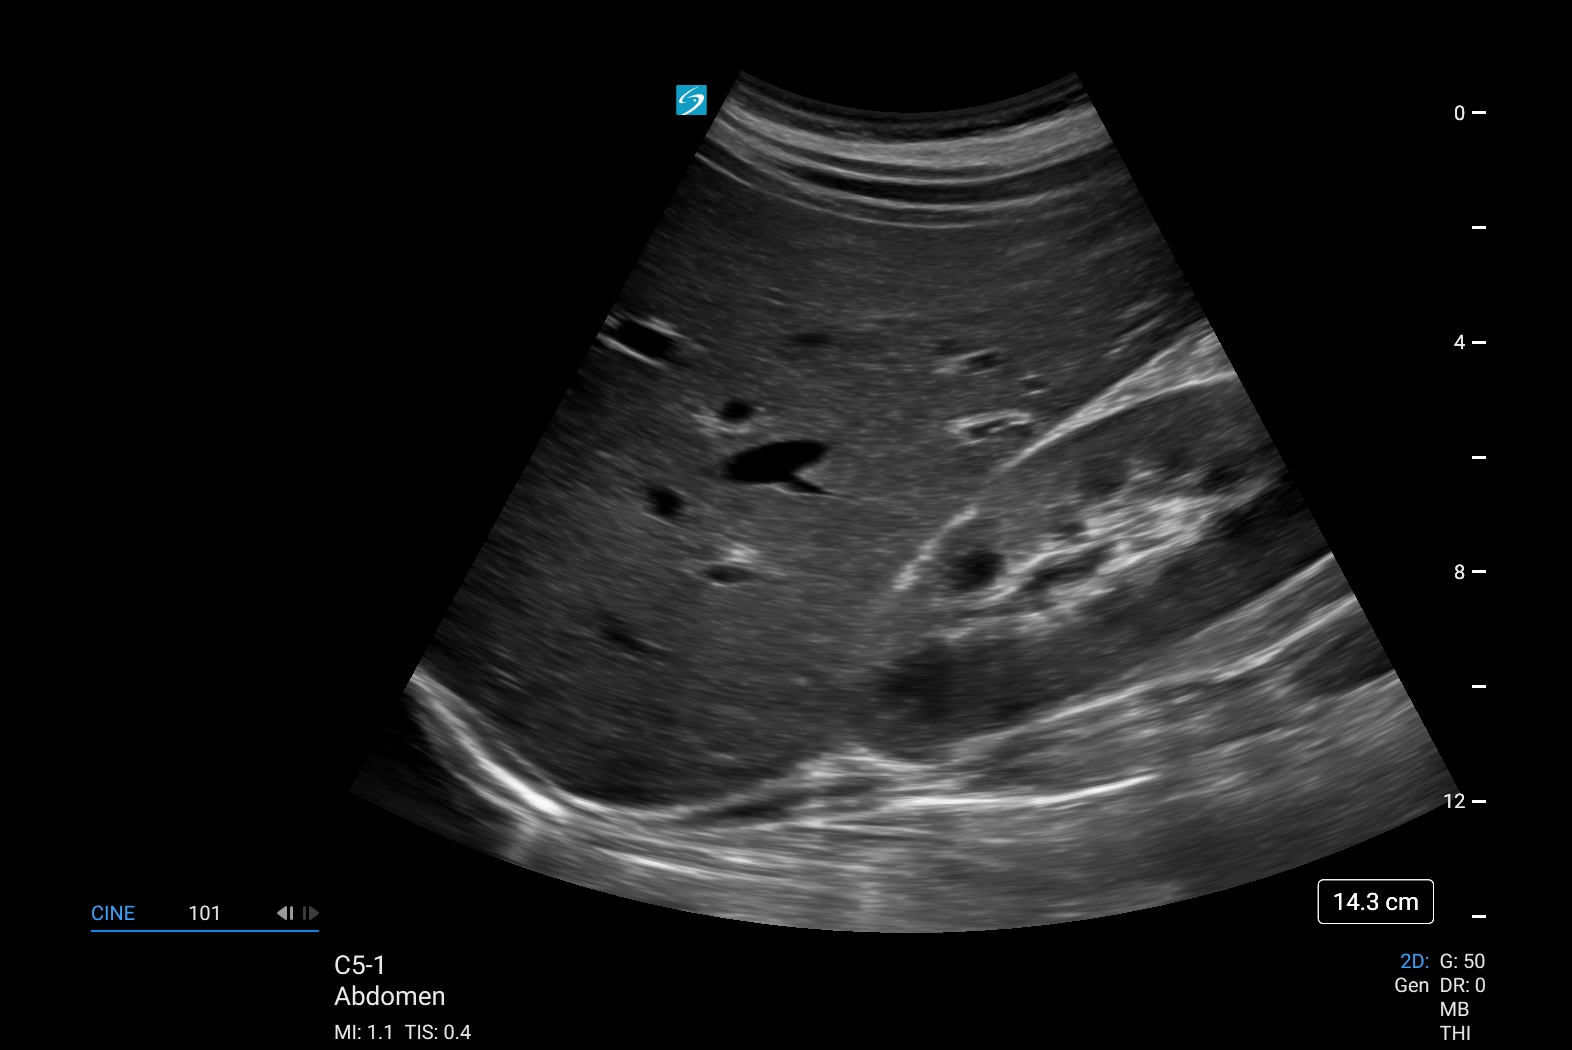

Sonosite LX, bakım noktası ultrasonunu çeşitli ortamlarda daha kapsayıcı ve erişilebilir hale getirerek klinisyenlerin deneyimini yükseltiyor. Sonosite LX, optimum hasta bakımı için en gelişmiş görüntü netliğimizi ve ses kontrolümüzü bünyesinde barındırıyor. Eğitim potansiyeliyle dolu olan bu ürün, her seviyedeki kullanıcıya her zamankinden daha fazlasını keşfetme gücü veriyor.

- Klinik ekip üyeleriyle kolay görüntüleme ve hastalarla konsültasyon için büyük, uyarlanabilir klinik ekranda gelişmiş görüntü netliği